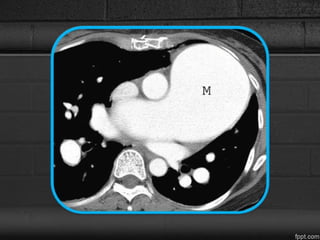

CT

• MPA >29mm, but not invariably, present.

• Size of the main pulmonary artery is more than the

ascending aorta at the level of base of the heart